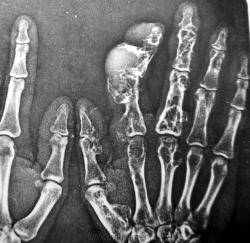

Пол пациента: Мужской пол Тип патологии: Врожденная патология Область исследования: Скелетно-мышечная система Методы исследования: Rg Думаю, что особых трудностей наблюдение вызвать не должно. Хотя... https://radiomed.ru/sites/default/files/styles/case_slider_image/public/user/1954/PICT3973.JPG?itok=5slXKF68 ID:343 Цель публикации: Консультация Вс, 17/01/2010 - 14:17 #1 Катенёв Валенти... Не на сайте Был на сайте: 7 лет 2 недели назад Зарегистрирован: 22.03.2008 - 22:15 Публикации: 54876 На мой взгляд, "картинка" даже более информативная, чем у Рейнберга. Вс, 17/01/2010 - 14:20 #2 Петрович Не на сайте Был на сайте: 7 лет 2 месяцев назад Зарегистрирован: 22.03.2009 - 01:13 Публикации: 3908 На первый взгляд множественные энхондромы. Неоднозначно всё Вс, 17/01/2010 - 14:31 #3 Анатолий Владим... Не на сайте Был на сайте: 7 лет 10 месяцев назад Зарегистрирован: 16.10.2009 - 21:16 Публикации: 1941 Тут оба вида роста во всей красе...

На мой взгляд, "картинка" даже более информативная, чем у Рейнберга.

На первый взгляд множественные энхондромы.

Неоднозначно всё

Тут оба вида роста во всей красе...